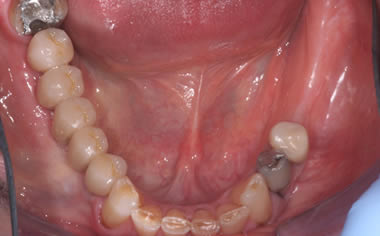

More back teeth replaced by dental implants

Case Three (2 images)

Case Four (4 images)